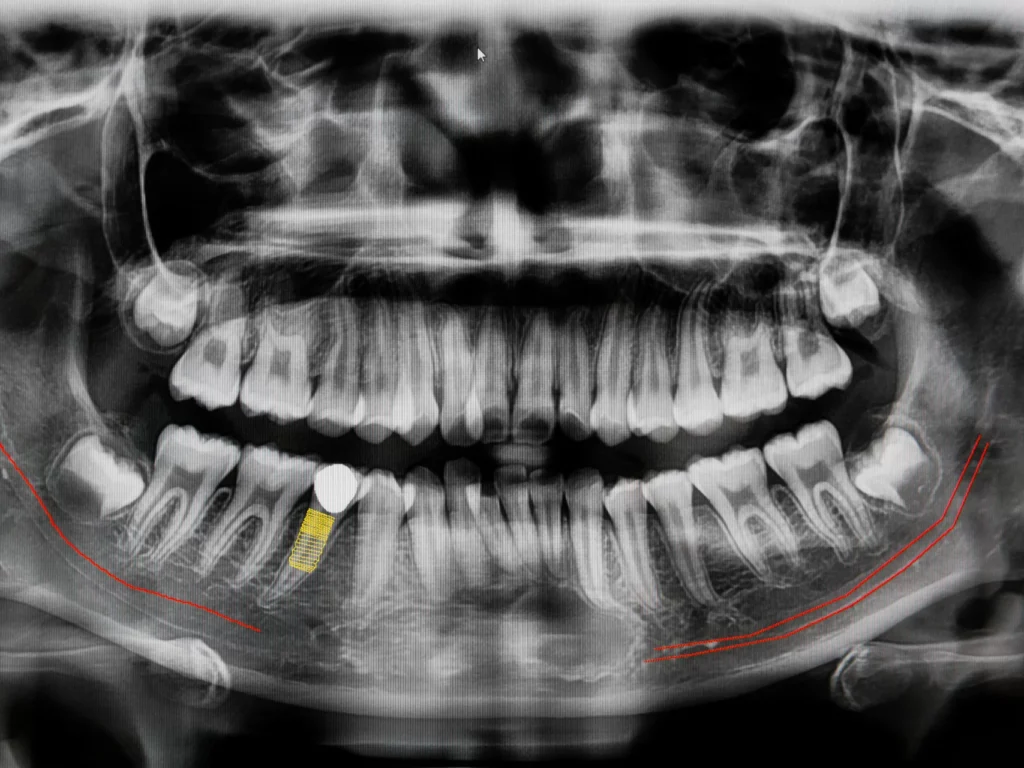

CBCT stands for ConeBeam Computed Tomography, which is a special type of digital x-ray scanner that dentists use to see a 3D image of your mouth and teeth.

The ConeBeam CT imaging system rotates once around your head while you stand or sit in a chair. The process is quick, simple, and completely painless. We use these scans to provide the best treatment in dental implants, root canals, diagnosis of dental and facial pain, etc.

We can evaluate your teeth and facial structures from literally every angle, in 3D, and in color! Routine x-rays, on the other hand, produce a single flat image with limited information.

You can have absolute confidence and satisfaction in the treatment you receive, knowing we’ve analyzed every problem with 3D technology.